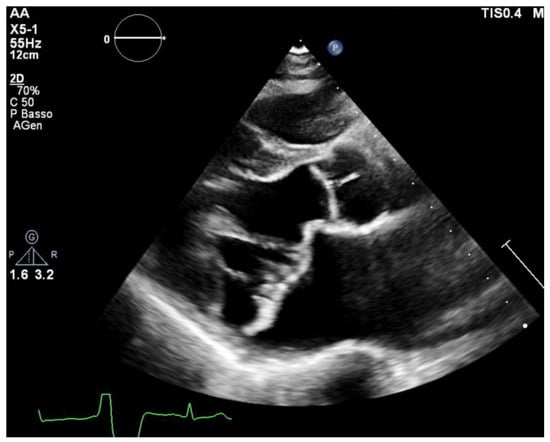

Mitral Valve Prolapse (MVP) is a pathology that affects up to 3% of the general population, and one third of this group has a form of prolapse involving both leaflets (bileaflet MVP or bMVP) [1,2]. Echocardiography is considered the gold standard imaging modality for MVP diagnosis. MVP is defined as a displacement of the mitral leaflets more than 2 mm into the left atrium during systole (Figure 1). Histologically, it can vary within a wide spectrum of types from the classical form (in which the leaflets have a maximal thickness of at least 5 mm during diastole) to the non-classical form with thinner leaflets due to a fibroelastic deficiency [3,4]. MVP prognosis can vary largely depending on multiple variables, such as the degree of mitral regurgitation (MR), left ventricular ejection fraction (EF), ventricular ectopics, atrial diameters and patient’s age [5,6]. Ever since its first description, MVP had been linked with ventricular arrhythmias (VAs) and sudden cardiac death (SCD) [6,7,8]. More recent observational studies have highlighted a concrete risk of SCD and sustained ventricular tachyarrhythmias, with an estimated annual risk ranging from 0.2% to 1.9% [9,10].

All of the patients underwent transthoracic echocardiography with ECG tracing. Echocardiography was performed using a Philips EpiQ CvX 7C echocardiograph with a Philips X5-1 3D probe. Every patient was screened with basal echocardiography, with careful morphological evaluation of the mitral valve (MV) and grading of the mitral regurgitation (MR) [13], along with a specific protocol to investigate tissue Doppler imaging of the mitral annulus, 3D imaging of the mitral valve and 3D full volume reconstruction of the ventricle. Bileaflet MVP was defined as the prolapse of both leaflets into the left atrium above the mitral annulus by at least 2 mm during the end-systole period, which is visualized in parasternal long axis view (PLAX), as shown in Figure 1 [14]. Mitral valve leaflets’ thickness and length were measured with 2D imaging in PLAX in meso-diastole, whereas the maximum height of the prolapse was measured during the end-systole period. Leaflet thickness was measured in diastole at the thickest point of the leaflet. Leaflets were defined myxomatous based on their morphology and thickness (greater than 5 mm). Antero-posterior and inter-commissural diameters of the mitral valve annulus (MVA) were measured in 2D in PLAX and in A2C views, respectively, both during the diastole and end-systole periods to investigate the presence of paradoxical systolic annular expansion [15]. Antero-posterior and inter-commissural diameters were also measured with 3D imaging, along with the MVA circumference and area. The anterior mitral leaflet (AML) length/AP diameter ratio was also calculated [13]. All of the anatomical parameters were tested at the baseline and after an adjustment for Body Surface Area (BSA). The Tissue Doppler Pulsed Wave (TDI-PW) was measured with an effort to optimize the ultrasound beam alignment with the longitudinal motion of the MVA on both the basal left ventricular segments displayed in the apical 4 chambers view (A4C), apical 2 chambers view (A2C) and apical 3 chambers view (A3C), thus providing 6 tracings for each patient. In this article, we refer to the “spiked systolic high-velocity signal” described by Muthukumar et al. as S3 [16], example shown in Figure 2. Absolute values of S1, S2 and S3 waves were measured. Mechanical dispersion was measured using the TDI, speckle tracking and Electro-Mechanical Window (EMW). The time from the onset of the R wave to the onset of the S1 wave, the end of S2/S3 wave, and the peak of S3 wave were measured using the simultaneous ECG monitoring to assess the presence of dyssynchrony by calculating the standard deviation of each time in all of the six TDI pulsed wave Doppler tracks within the same patient [17]. The speckle tracking (STE) analysis was performed on the workstation using the software CMQ 10 for Q-LAB, and global longitudinal strain (GLS) was calculated using the A4C, A2C and A3C views with a good display of the endocardial border. The endocardial border was outlined by a single operator at the end-diastolic phase of the cardiac cycle. Minor adjustments were made to optimize tracking throughout the cardiac cycle. Mechanical dispersion (MD) was calculated as the standard deviation (SD) of the times measured from the onset of R on the ECG to the peak strain (TPS) in each of the 18 segments of the left ventricle, and sub-analyses were performed separately considering the basal segments alone, the mid-ventricular segments alone, the apical segments alone and basal segments combined with middle segments as well. The transversal shift measured by CMQ 10 using Q-LAB software was analyzed as well in order to quantify the transversal motion of the ventricular walls throughout the cardiac cycle. Additionally, the GLS pattern was analyzed to research a specific double peak pattern that is suggestive of arrhythmic events and dyssynchrony.

Figure 1. A parasternal long axis (PLAX) view of MVP in end-systole from a patient enrolled in the aMVP group. Note the prolapse of both leaflets above the mitral annulus plane.